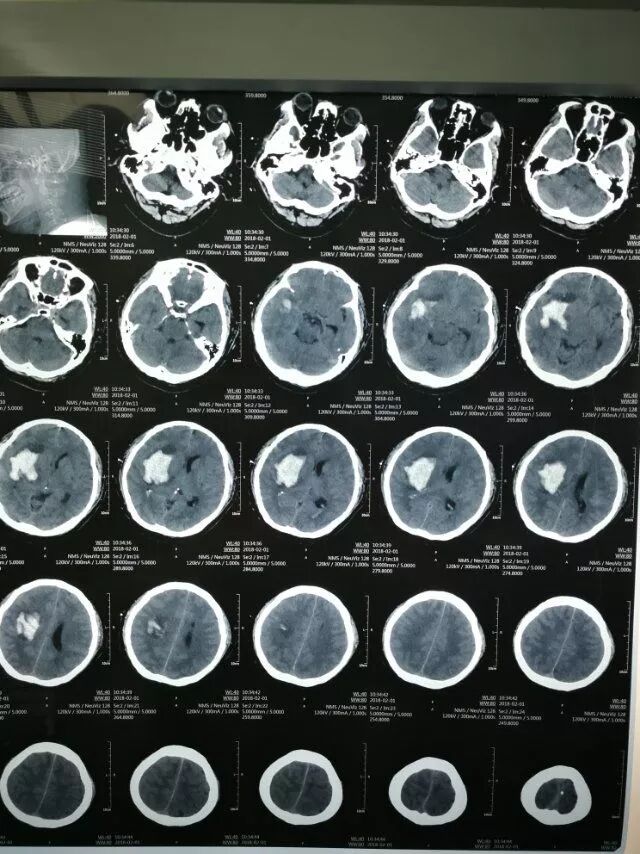

患者男性,48岁,脑出血发病2小时入院。神志模糊,继发脑疝,头CT:右侧基底节出血量约60毫升。

术后第一天复查